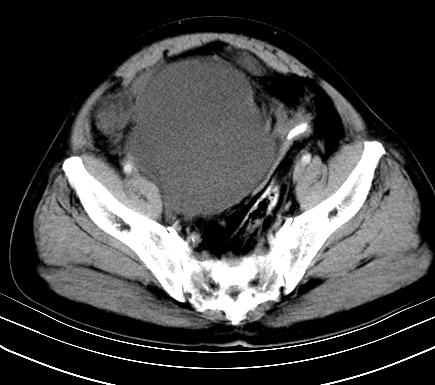

增强扫描

动脉期

【ct表现】

1、肿块巨大,往往位于腹膜后,长大后才引起症状而就诊;那么位于腹膜后的肿瘤80%为恶性肿瘤。

2、实性肿瘤,增强扫描轻度不均强化,实性肿瘤一般不是好东西。

3、肿瘤边缘似见少许脂肪样密度。

4、腹膜后未见肿大淋巴结,但肿瘤于临近的肠管及组织接触紧密。

【诊断】

腹部占位,考虑位于腹膜后的恶性肿瘤,脂肪肉瘤(实体型)可能性大。

【分析】

1、腹膜后的肿瘤少见,但种类繁多,包括脂肪肉瘤、纤维组织细胞肉瘤、纤维肉瘤、平滑肌肉瘤、恶性畸胎瘤、神经肉瘤、神经母细胞瘤、血管肉瘤及横纹肌肉瘤等,其中脂肪肉瘤为较常见的一种肿瘤。

2、增强扫描强化不明显,除脂肪肉瘤以外,一般肿瘤强化中度以上。脂肪肉瘤可不强化或轻度强化。

术后病理结果:腹膜后脂肪肉瘤。